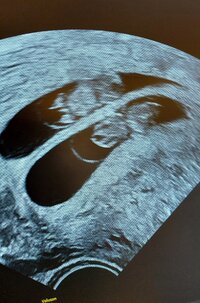

Ai juu nyt muistan! Hyvä, että ei ollut lähellä pikkusta. :) Kiva, että pääsee vielä kontrolliinkin!Taisin tonne yleiseen höpinään kirjoittaa. Että viime to alkoi hennon vaaleanpunainen vuoto ja soitin sitte omalle gynelle, että pääsisinkö tällä viikolla tsekkaa tilannetta hänelle. Hän kuitenkin järkkäsi lauantaiksi ajan ja kävin tsekkaamassa tilanteen. Siellä näkyi pieni riisinjyvä sykkeellä, mutta mittoja ei saatu kun oli niin pieni vielä. Lisäksi siellä on noin 1,5cm kokoinen hyytymä, joka nyt vuotaa. Lääkäri lohdutti, että olisi tarpeeksi kaukana riisinjyvästä, että ei veisi sitä mennessään. Mutta nyt odotellaan. Viikon päästä seuraava kontrolli omalle gynelle, niin en nähnyt tarpeelliseksi mennä varhaisultraan kätilölle![]()

TuplaonneaPäästiin kunnalliselle tarkistamaan viikot ja yllätys pomppasi ruudulle! Tuplat!![]()

Paljon onnea!Päästiin kunnalliselle tarkistamaan viikot ja yllätys pomppasi ruudulle! Tuplat!![]()